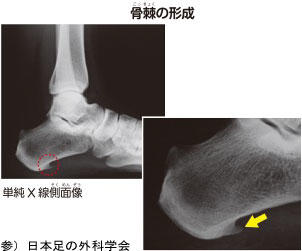

足底腱膜の緊張を長期間放置しておくと、かかとの骨(踵骨)の足底腱膜付着部に、

石灰化、骨化といった骨棘という骨のトゲが形成されえる場合があり、

痛みの長期化に繋がる場合が多々あります。